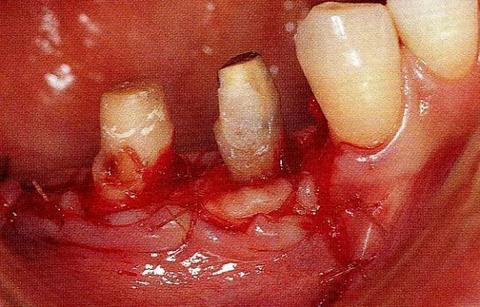

圖17-3   拔牙的同時(shí)做骨外科處理,讓殘留的骨可以盡量平坦化。為了獲得頰側(cè)的附著齦,采用了游離齦瓣的處理。